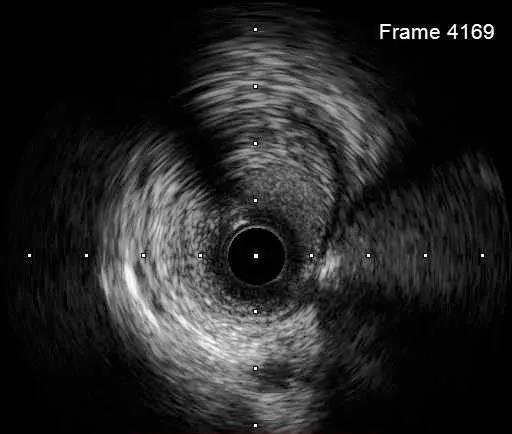

DEB bingo 2.5*30mm 10atm 结果满意

IVUS-3